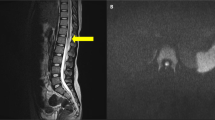

An initial MRI scan of the brain obtained 3 days after the accident revealed an abnormally high signal in the white matter (Figure 3). This had resolved on repeat MRI performed 8 weeks after the injury. Also, an MRI of the cervical spine performed 3 days after the accident showed an abnormally high signal at C3–4 level (Figure 4), which then disappeared on repeat scan 10 weeks later.

(a) This is a saggital T2 weighted MRI scan of the cervical spine taken 3 days postinjury. It depicts an abnormal high signal at the C3–C4 of the spinal cord. There is also a disc herniation at C5–C6 disc space but with No cord signal (no axial images were taken at this stage). (b) This is a T2 axial MRI image of the cervical spine taken 10 weeks after the accident. It depicts a small right-sided disc herniation at C5–C6 level, some alterations in signal are present in the C5–C6 vertebrae, however; there is no evidence of cord lesion at this level